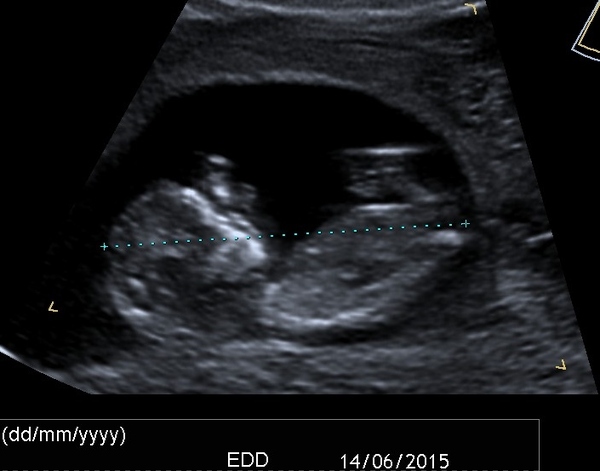

I've just had a long FaceTime chat with my daughter and now have a little more information. She is currently Grade III placenta previa and has been told to do no lifting, no intercourse etc. I think because of the ongoing bleeding (was listening and trying not to ask questions). The last two scans were 'viability' scans and having seen them the baby looks fine to my untrained eye, but my daughter is concerned about the effects of ongoing bleeds on the baby's development. The place she lives is quite some distance from a hospital so she's happy to continue working on light duties for as long as possible on the basis that she actually works in a hospital and will therefore be in the best place if she needs attention.